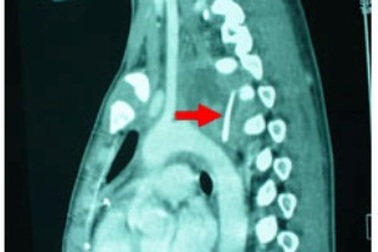

Xương gà xuyên thủng thực quản, bệnh nhân suýt tử vongNhập viện trong tình trạng sốt cao, đau tức ngực, ho khạc ra máu,… qua chẩn đoán hình ảnh, bác sĩ ghi nhận bệnh nhân bị hóc xương gà gây thủng thực quản. Không thể gắp xương bằng nội soi, bác sĩ buộc phải mổ cấp cứu lấy mảnh xương dài 3cm cứu bệnh nhân.

Suýt tử vong vì xương gà đâm thủng thực quản, phế quảnNhập viện trong tình trạng sốt cao, đau ngực, khó thở… qua chẩn đoán hình ảnh, bác sĩ ghi nhận bệnh nhân bị hóc xương gà gây thủng thực quản, phế quản. Không thể gắp xương bằng nội soi, bác sĩ buộc phải mổ cấp cứu lấy mảnh xương dài 3cm cứu bệnh nhân.